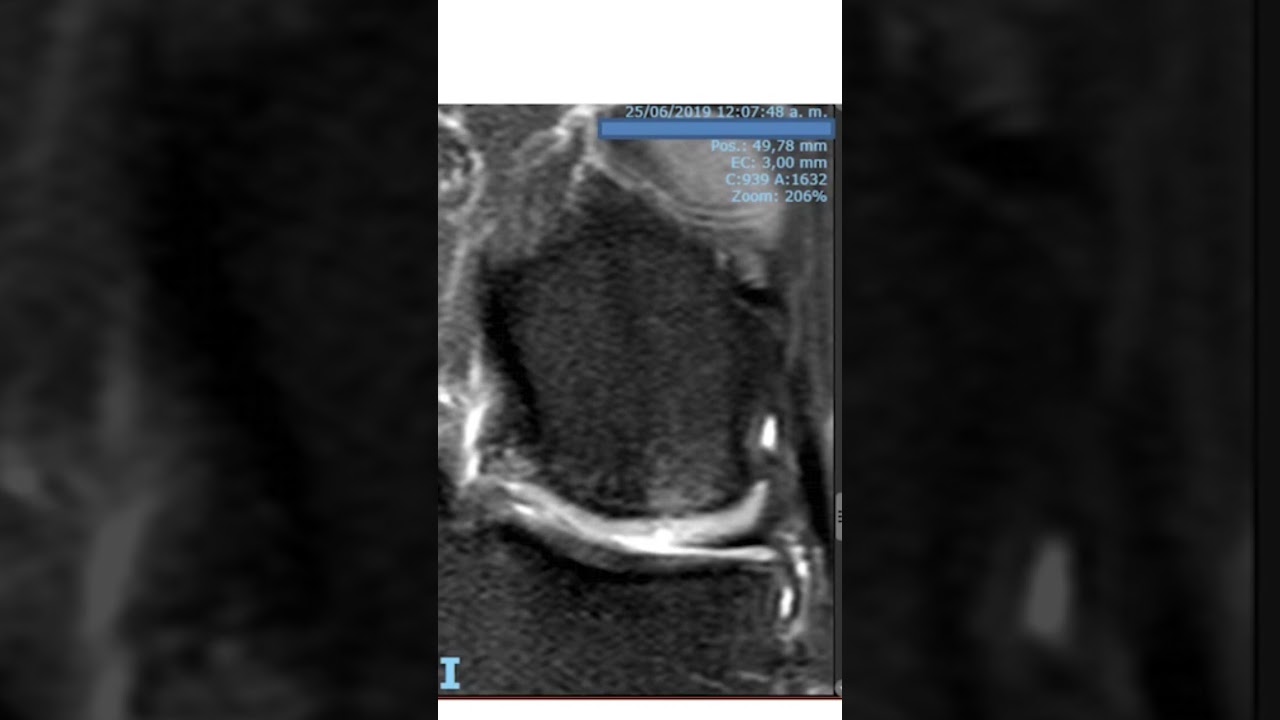

WebLa artrosis se puede producir en cualquier articulación, pero sus localizaciones mĆ”s frecuentes son la cadera, la rodilla, la columna y las articulaciones interfalĆ”ngicas. WebLa artrosis es la pĆ©rdida del cartĆlago en una articulación y el desarrollo de mecanismos de defensa por parte de nuestro organismo en esa articulación para. WebRodilla con artrosis – Rodilla con prótesis En Advansur somos expertos en traumatologĆa avanzada y son muchos los casos de artrosis de rodilla que hemos. WebINTRODUCCIĆN. La resonancia magnĆ©tica (RMN) como terapĆ©utica del dolor producido por la artrosis es un concepto relativamente nuevo. Se ha desarrollado a partir de. WebLo que sucede en la artrosis de rodilla es que el cartĆlago de la articulación pierde la capacidad para regenerar sus propias cĆ©lulas (llamadas condrocitos) haciendo. WebEl propósito de este artĆculo es mostrar un mĆ©todo de estudio del cartĆlago articular de la rodilla para ser empleado en un equipo de resonancia magnĆ©tica de 3.0 Teslas (T). El. WebLa artrosis de rodilla es el desgaste del cartĆlago articular de la articulación de la rodilla. Este desgaste, genera dolor y a veces crepitaciones en la rodilla. Es bastante comĆŗn y. WebTratamiento y prevención del dolor de rodilla. Con todos estos sĆntomas y causas en mente, es posible que te preguntes cómo tratar y prevenir varias de estas lesiones. Una vez que. WebEl procedimiento para MRI de la articulación de la rodilla dura 30 minutos. La lectura directa de la información de MRI dura aproximadamente 15 minutos. La.

Actualmente - Resonancia MagnĆ©ticas de lesión de rodilla por osteoartrosis Ćltimo